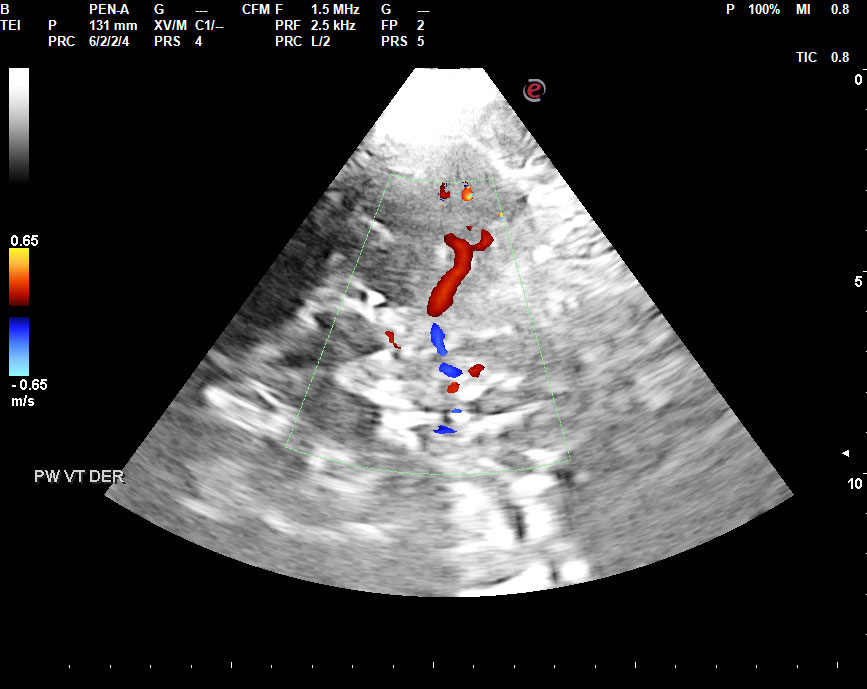

- Isquemia: Disminución en la llegada de sangre a una zona concreta del sistema nervioso, habitualmente por interposición de un trombo (coágulo que se forma localmente) o émbolo (coágulo u otro elemento físico que se genera en otra localización y circula por el torrente sanguíneo hasta ocluir una arteria). Esta a su vez puede ser: